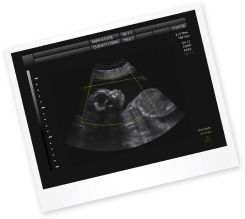

УЗИ в срок 35 недель беременности

Врачи постоянно контролируют состояние здоровья будущей мамы и развитие малыша. Для того, чтобы подтвердить, что кроха чувствует себя хорошо, назначается УЗИ-исследование. В этот период оценивается состояние плаценты, так как она отвечает за снабжение плода питанием и кислородом. К сроку 35 недель она должна иметь вторую степень зрелости.

Также врач определяет вес плода и его рост, соответствие уровня развития плода сроку беременности. Врач проводит осмотр всех органов плода, прослушивает сердцебиение, чтобы подтвердить отсутствие каких-либо патологий.

В этот период необходимо оценивать объем и состояние околоплодных вод. Врач определяет их объем, измеряя определенные показатели. Также оценивается предлежание плода. Если малыш расположен в тазовом предлежании, это позволит врачу продумать тактику ведения беременности и предстоящих родов.